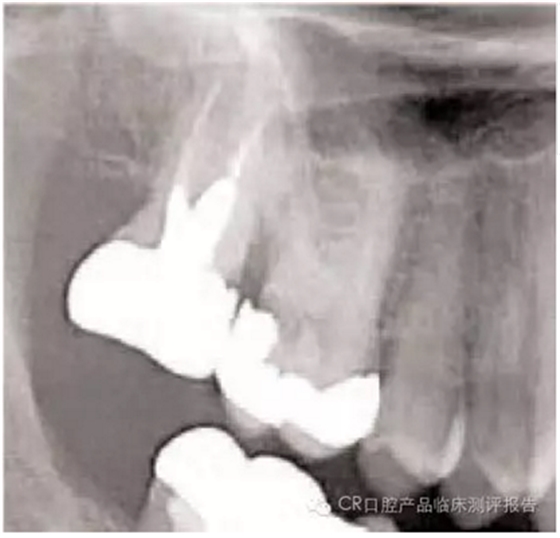

● 影像學(xué)檢查的要點(diǎn)

- 包括根尖:注意根尖的形狀(喇叭口、彎曲、融合、球形),有些情況需要牙根縱切。

- 找出牙根附近重要組織的影像:牙周膜(PDL)的缺口、上頜竇、血管神經(jīng)、高密度骨質(zhì)區(qū)域。根內(nèi)是否含有根管?(觀察比較難因?yàn)楦芤姿榛蚺c骨長(zhǎng)合)

病例

4. 在不觸碰鄰牙的前提下,牙根不在上頜竇內(nèi)的情況下(需拍x線片確認(rèn),放置根間有竇腔),可以用702車(chē)針將復(fù)雜牙齒的腭根和頰根分開(kāi)。